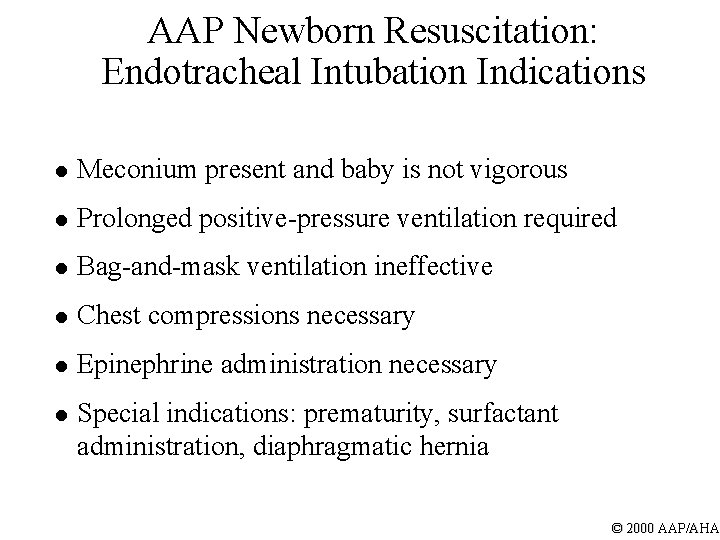

AAP Newborn Resuscitation: Endotracheal Intubation Indications l Meconium present and baby is not vigorous l Prolonged positive-pressure ventilation required l Bag-and-mask ventilation ineffective l Chest compressions necessary l Epinephrine administration necessary l Special indications: prematurity, surfactant administration, diaphragmatic hernia © 2000 AAP/AHA